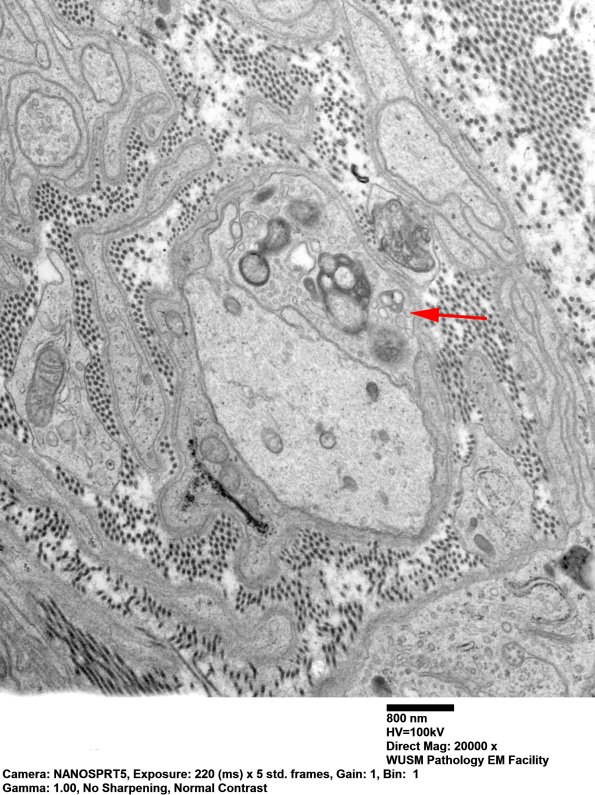

The demyelinated axon is immediately adjacent to a Schwann cell with cytoplasmic myelin debris (arrow). (electron micrograph)